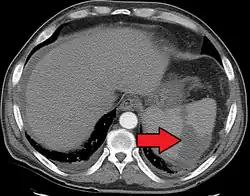

Splenic infarct seen on CT | |

Splenic infarction is a condition in which blood flow supply to the spleen is compromised,[1] leading to partial or complete infarction (tissue death due to oxygen shortage) in the organ.[2] Splenic infarction occurs when the splenic artery or one of its branches are occluded, for example by a blood clot.[3]

An abdominal CT scan is the most commonly used modality to confirm the diagnosis,[3] although abdominal ultrasound can also contribute.[5][6][7]